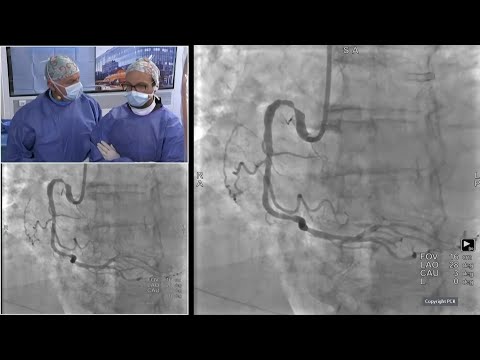

Transradial approach for complex PCI in a high bleeding risk (HBR) patient - Webinar In The Lab

Management of a High Bleeding Risk (HBR) patient with a bifurcation lesion - Webinar In The Lab